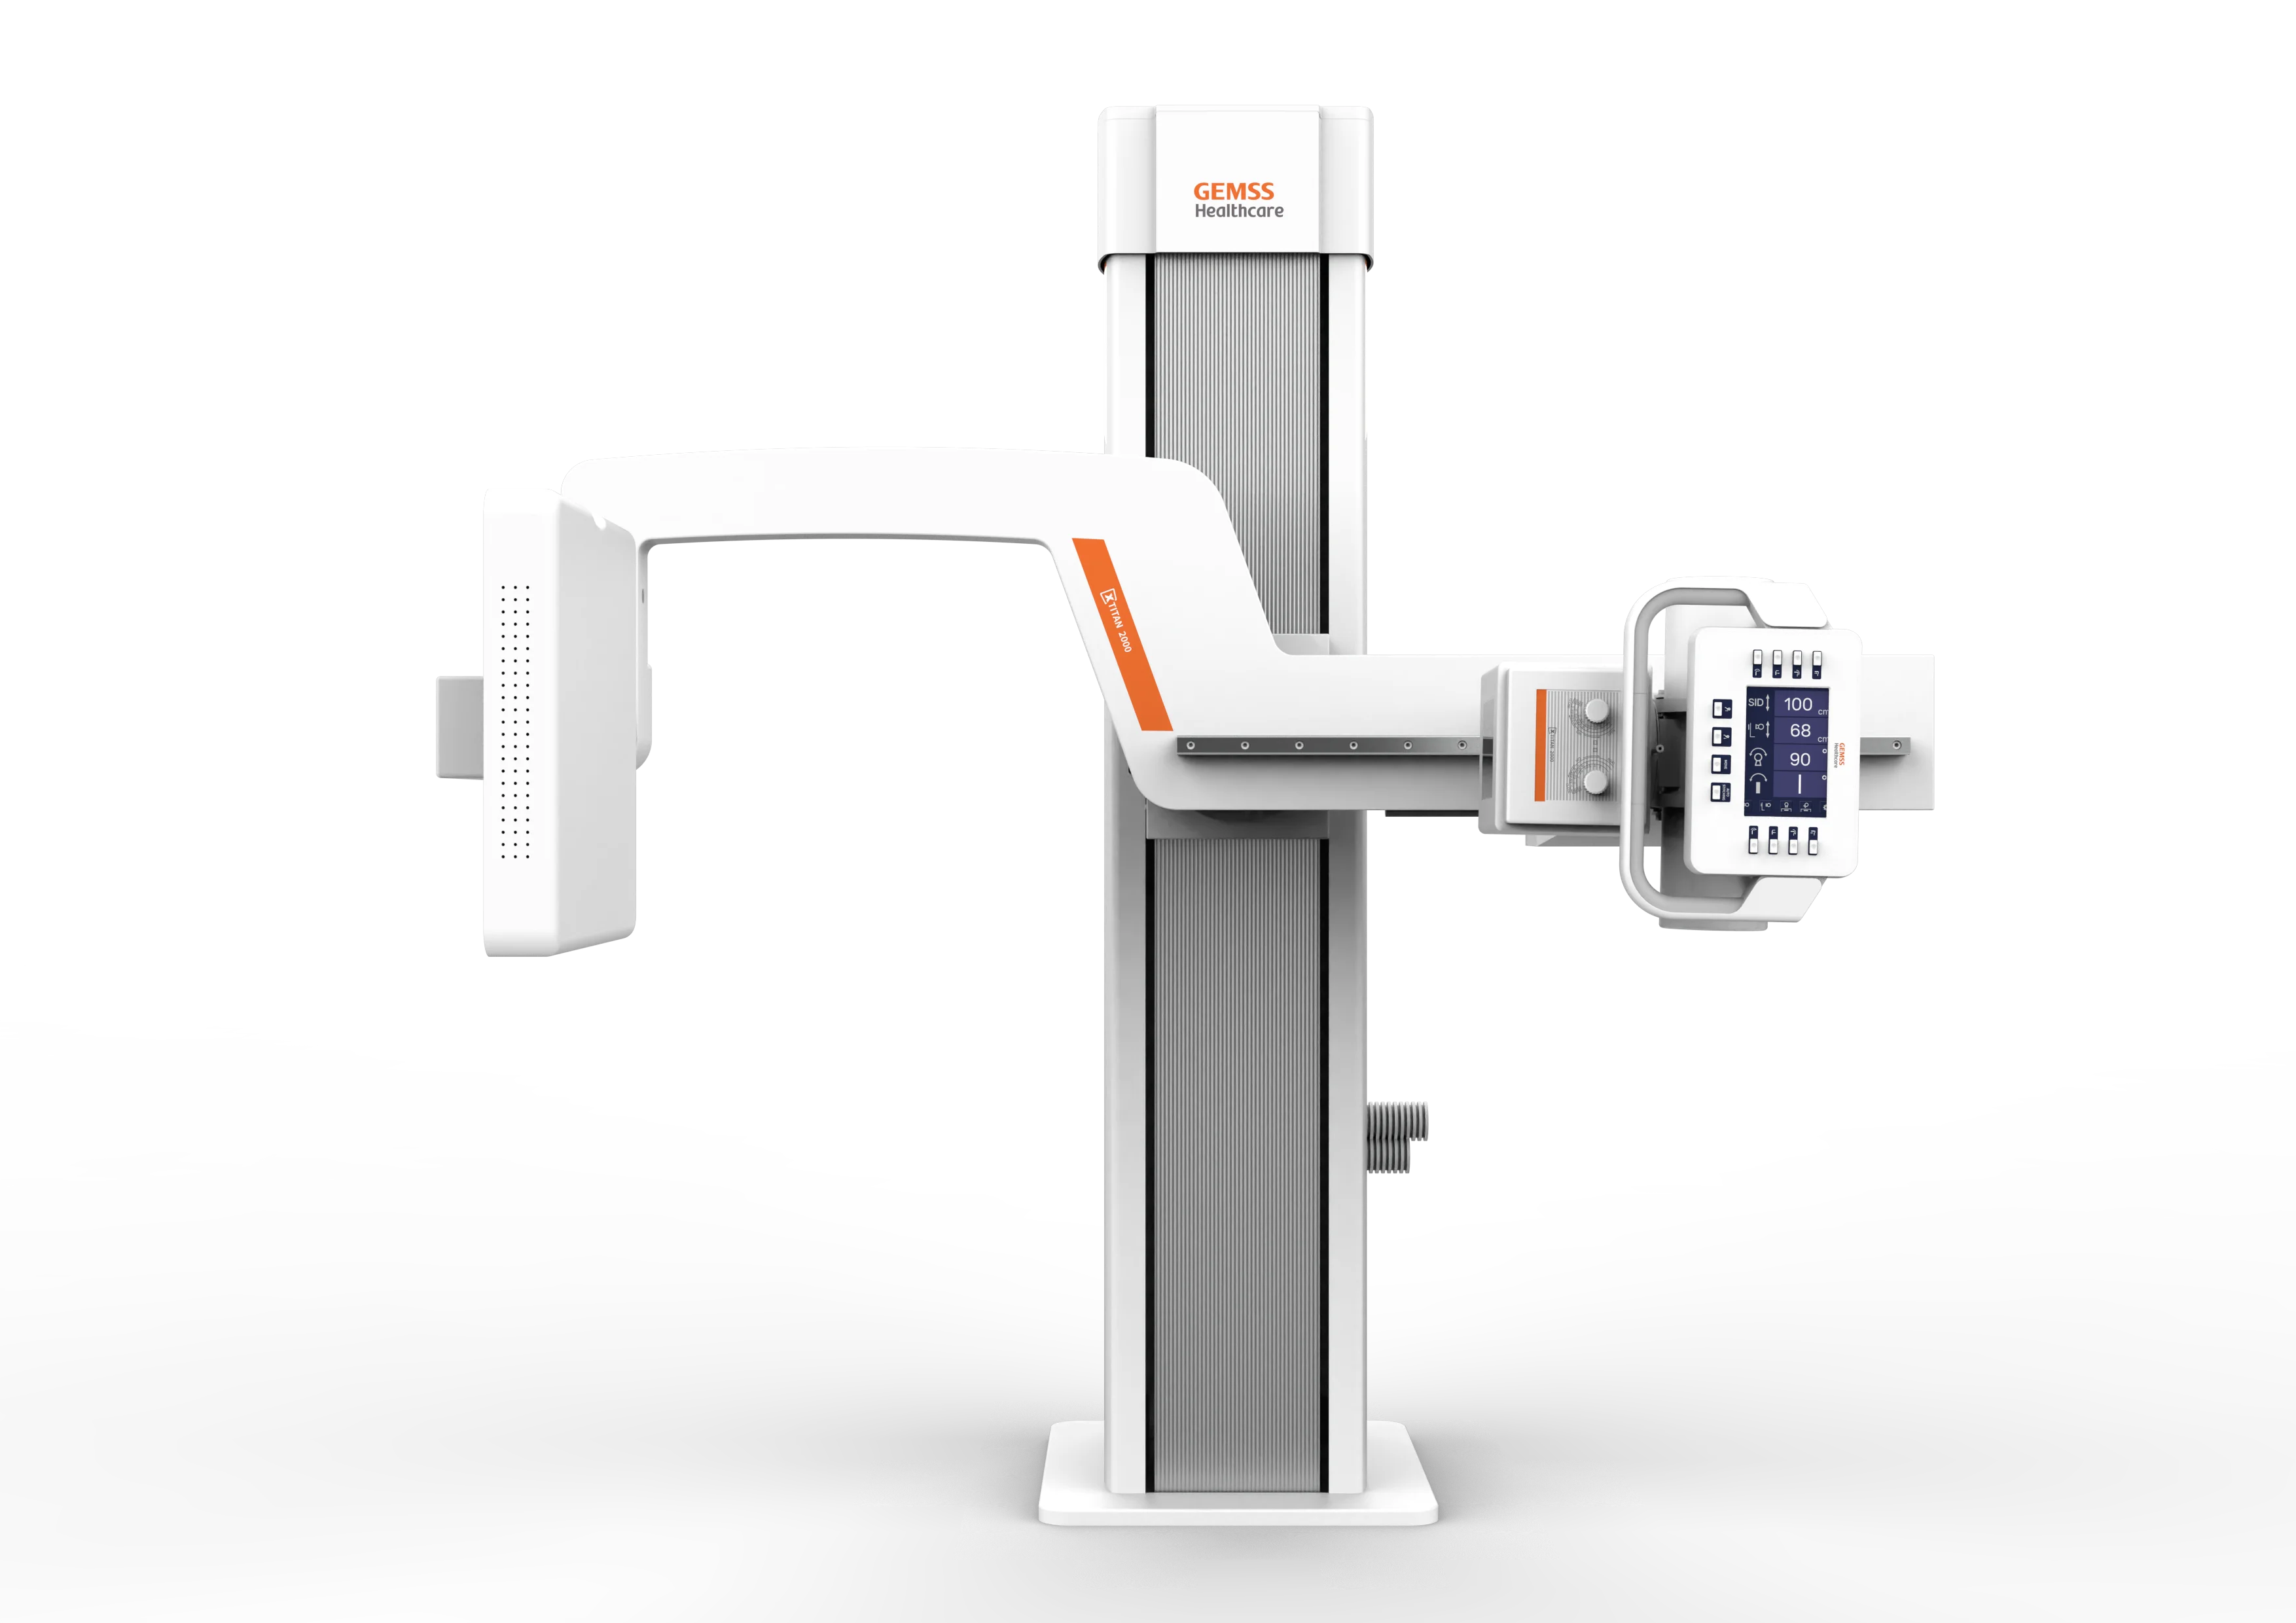

Рентгеновский аппарат типа U-дуга GEMSS TITAN UNIVERSAL

Универсальная цифровая рентгено-графическая система Titan Universal c плоскопанельным детектором предназначена для медицинских учреждений с высокой проходимостью пациентов и позволяет проводить исследования в вертикальных и горизонтальных проекциях.

Рентгеновский аппарат Gemss Medical Systems Titan Universal U-Arm представляет собой высокотехнологичное решение для медицинских учреждений, обеспечивающее точную и эффективную диагностику. С его помощью можно проводить широкий спектр рентгенографических исследований благодаря универсальной конструкции и современным технологиям.

- Универсальный U-Arm: Позволяет выполнять рентгенографию в различных позициях, обеспечивая гибкость и удобство в работе.

- Компактный дизайн: Идеально подходит для использования в ограниченных пространствах медицинских учреждений.

Компактная конструкция

Механическая конструкция требует минимального пространства, подходит для помещений от 15 м^2